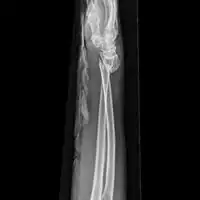

Front view of bowing fractured radius and ulna

Side view of bowing fractured radius and ulna